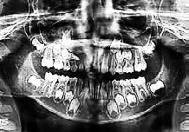

Se presenta una paciente clase ll esquelética en los estudios extrao rales en la fotografía de frente se ve hiperdivergente con una mordi da profunda de 5mm, un diastema, y refiere como motivo de consulta "no me gusta el espacio entre mis dien tes" (Figura 1).

En los estudios intraorales de inicio en las fotografías se muestra en la de frente el diastema anterior, con la línea media dental superior e inferior no coincidentes, la mordida profun da anterior (Figura 2), en la lateral derecha clase l molar y canina bila teral (Figura 3), el apiñamiento leve superior e inferior y la forma de las arcadas.

Estudios radiográficos iniciales

En la radiografía lateral de cráneo se ve el diagnósitico: clase II esqueléti ca, con crecimiento hiperdivergente, mordida profunda anterior (Figura 4).

En la radiografía panorámica se observa 28 piezas dentales, con un diastema en los incisivos centrales (Figura 5).

Figura 1. Extraoral de inicio de frente. Figura 2. Intraoral de frente derecha, izquierda. Figura 3. Oclusal superior e inferior arcadas cuadrada. Figura 4. Radiografía lateral de cráneo. Figura 5. Rx Panorámica.